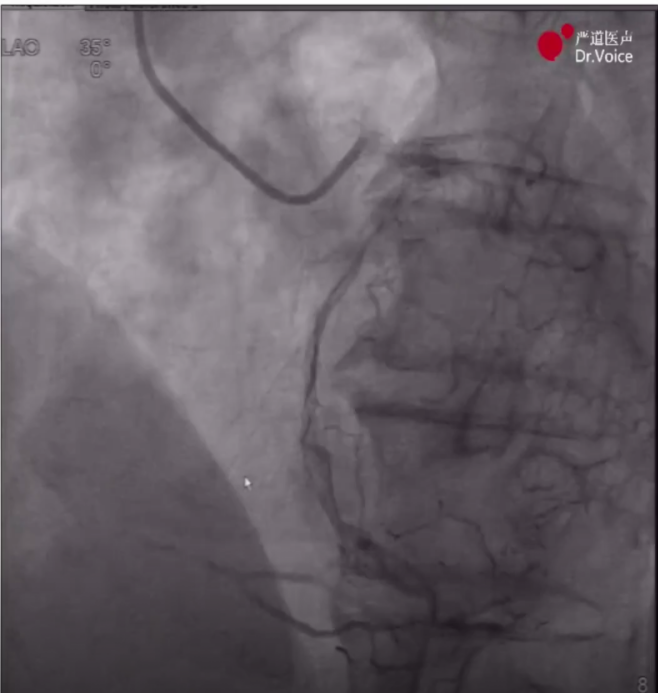

1、术前造影显示LAD弥漫病变、中段完全闭塞,LCX原支架血流通畅,RCA血管纤细、中段完全闭塞,远段侧枝循环形成。

LAD造影图像

RCA造影图像